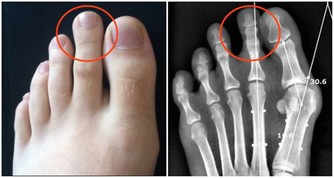

痛風患者不應多喝海鮮湯等,因為其中的嘌呤含量較高。